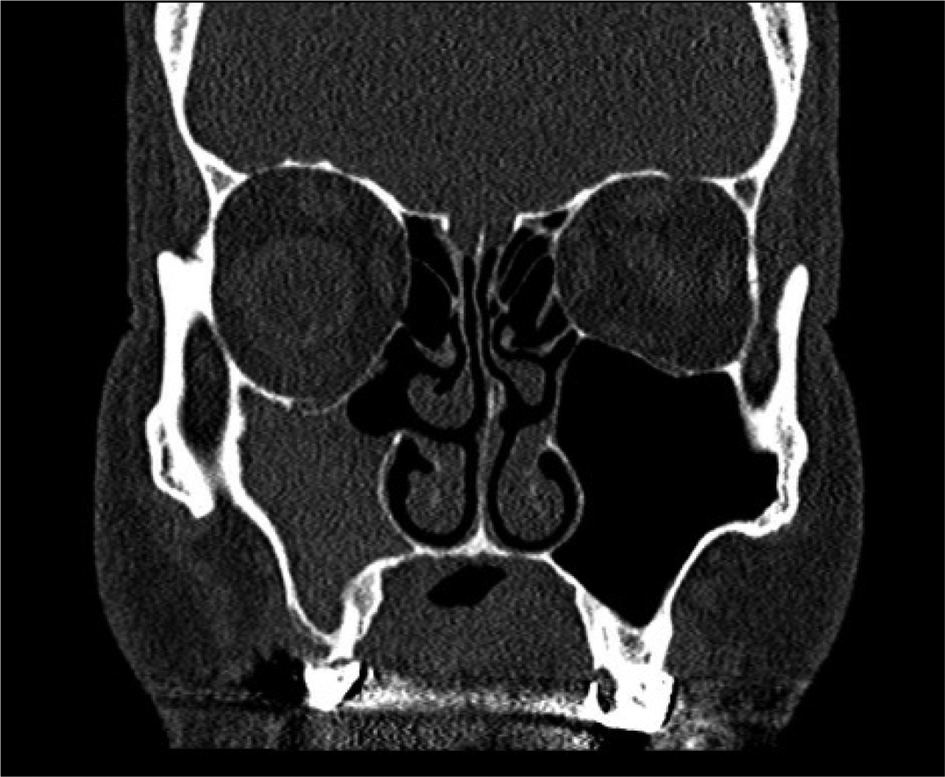

General symptoms of sinusitis were present in 21 patients and absent in 33 patients. Eleven patients had grade I (Figure 1), 35 patients had grade II (Figure 2) and 8 patients had grade III (Figure 3) chronic maxillary atelectasis. Seven patients met the silent sinus syndrome criteria; one patient with chronic maxillary atelectasis grade III was symptomatic and therefore not considered to have silent sinus syndrome. Table 2 reports the clinical features.

Fig. 3. Coronal computed tomography scan of the paranasal sinus demonstrating downward displacement of the orbital floor and right maxillary sinus opacity (right) (grade III chronic maxillary atelectasis).